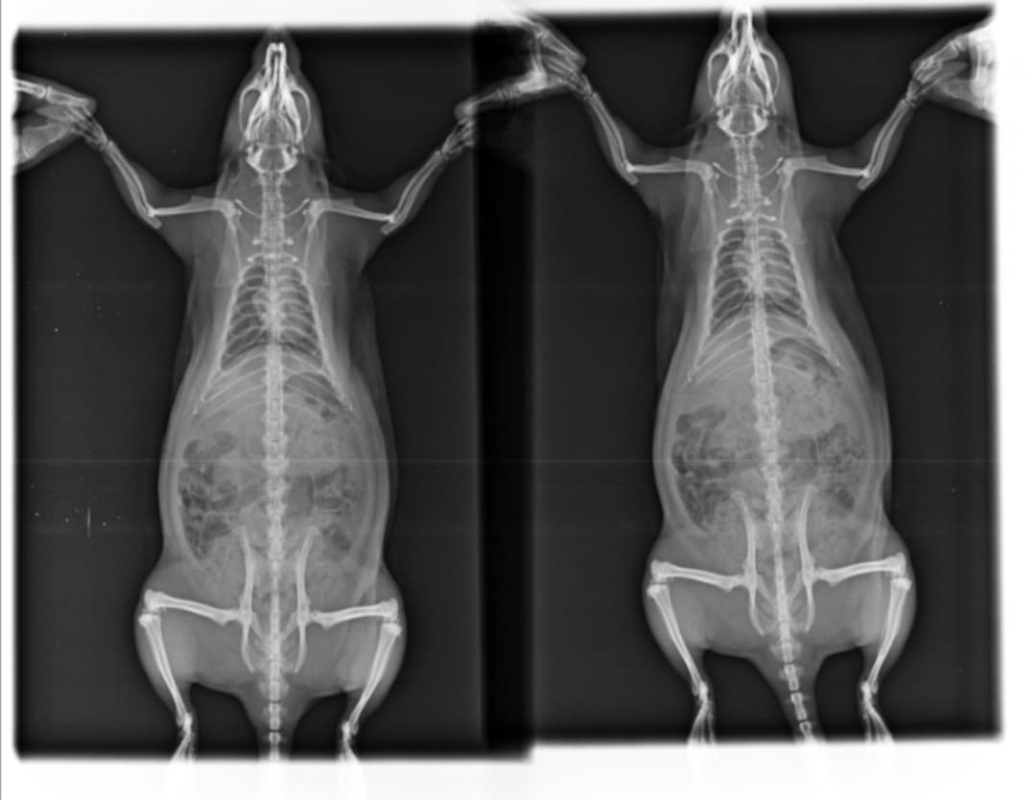

Je mets les radios, Mathilde n'arrive pas à les charger:

Radio du 5 mai:

Les radios sont pas terribles, pas très bien exposées ni assez centrées sur la cage thoracique et floues, du coup perso j'arrive pas à voir grand chose >< Mais bon tes vétos ont sans doute davantage l'habitude. Par contre je trouve aussi que le cœur est gros.